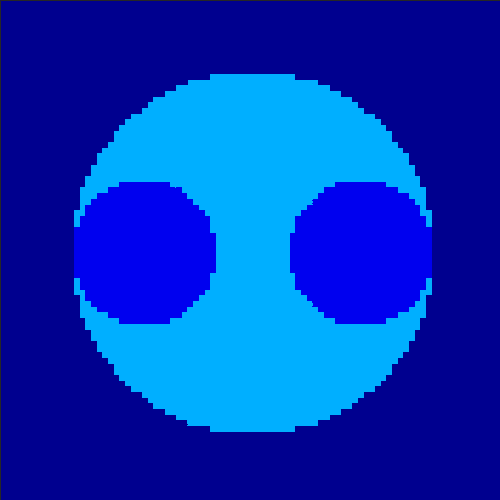

5.2 Monte Carlo Simulation

In order to test the behaviour of the proposed method in a more realistic, random-based test case, we performed a Monte Carlo simulation for dynamic SPECT imaging. First, we created a simple image phantom consisting of an outer and two inner circles which represents the structure of the region of interest (see figure 8(a)). Within those regions we assumed concentration curves over a time period of 90 time steps as displayed in figure 8(b). Based on the tracer intensity in an image frame at each time step, we created a variable number of random decay events (where the number is proportional to the average concentration in one pixel in the whole image frame per time step) with a probability proportional to the concentration in every subregion. They are detected by a virtual double head gamma camera rotating around the patient by 46 degrees per time step, which consists of 374 detector bins. Every simulated decay event is projected onto the scanner and counted by the corresponding detector bin.

In two different tests we fixed the number of events counted by the detector equal to (resp. ) times the average concentration in one pixel. The resulting sinogram images of the accumulated counts in each bin are shown in figure 9.

Based on the sinogram data we applied the proposed algorithm in order to reconstruct the original image sequence. The results for both test cases are shown in figure 10.

As one can see, the method is able to reconstruct the regions properly, even in case of a low count number. Within a number of iterations (average of 100 outer and 10000 inner iterations), the algorithm presents a reasonable reconstruction of the region of interest and the corresponding regional tracer concentration curves. Here, the parameters were not optimized as in the case of the synthesized data sets in the previous section, but kept fixed as , and . With futher optimized parameter values one could possibly provide even better results.